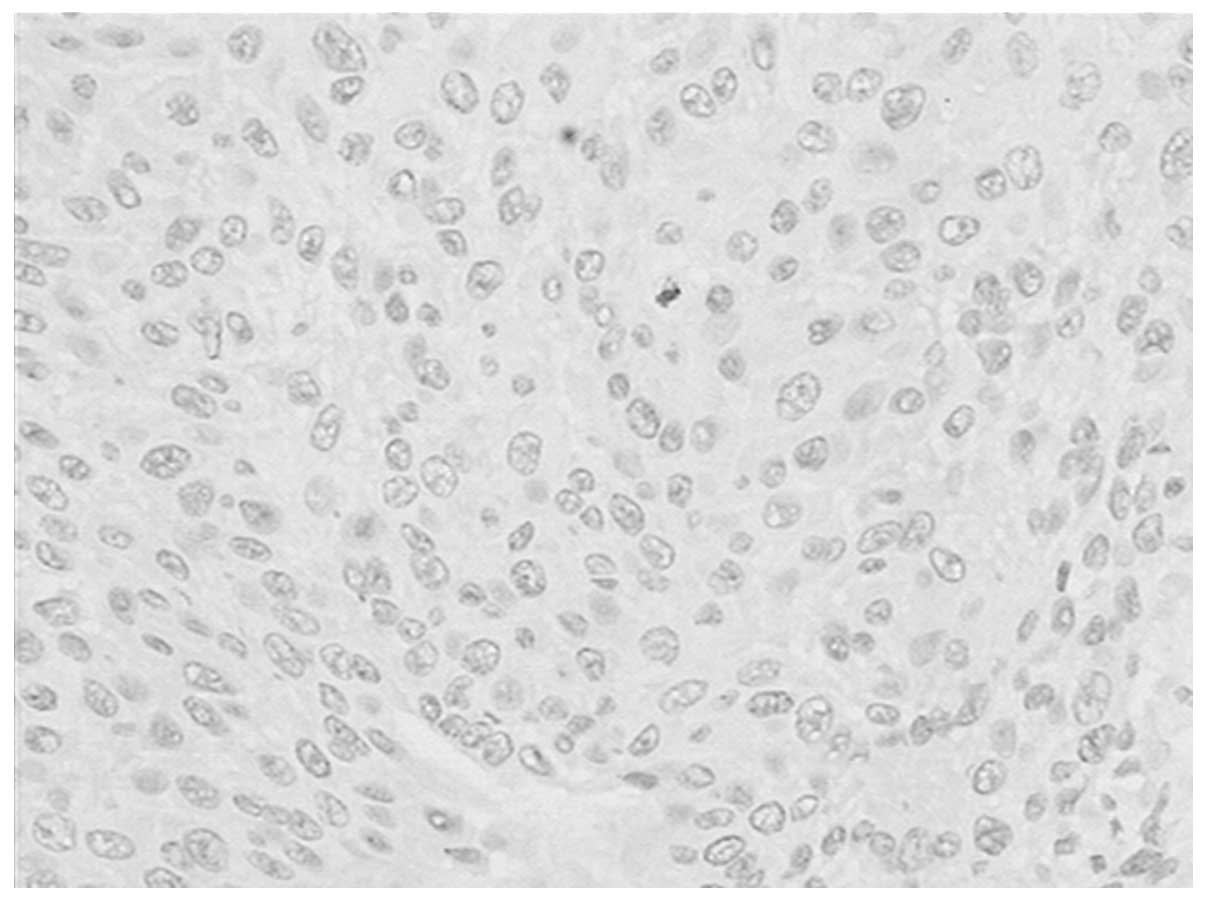

Correlation of CD146 expression and clinicopathological characteristics in esophageal squamous cell carcinoma

CD146, a cell adhesion molecule, is found in normal and tumor tissues. The level of its expression has been found to directly correlate with tumor progression and metastatic potential. The objective of this study was to investigate the expression of CD146 in esophageal squamous cell carcinoma (ESCC) and its correlation with clinicopathological parameters. Tumor specimens were collected from 63 patients with ESCC who underwent complete resection. We analyzed the CD146 expression levels in ESCC by immunohistochemistry. The expression of CD146 was detected and it was observed to correlate with clinicopathological parameters. Sixty‑three cases of normal squamous mucosa were included for comparison. CD146 expression was identified in 46.0% (29/63) of the ESCC samples, and no positive (weak to moderate or moderate to strong) expression was found in the normal squamous epithelium samples (χ2=27.248; P<0.0001). CD146 expression was associated with lymph node metastasis (χ2=5.117; P=0.024) and advanced clinical stage (χ2=4.661; P=0.031). CD146 expression was one of the significant predictors of survival (hazard ratio, 2.838; 95% confidence interval 1.102‑7.305). The overexpression of the CD146 gene was one of the important phenotypes and characteristics in ESCC carcinomatous change. We found that CD146 expression was associated with lymph node metastasis and advanced clinical stage, and was an indicator of poor prognosis in ESCC patients. CD146 may prove to be an important tumor marker for the individualized treatment for ESCC.